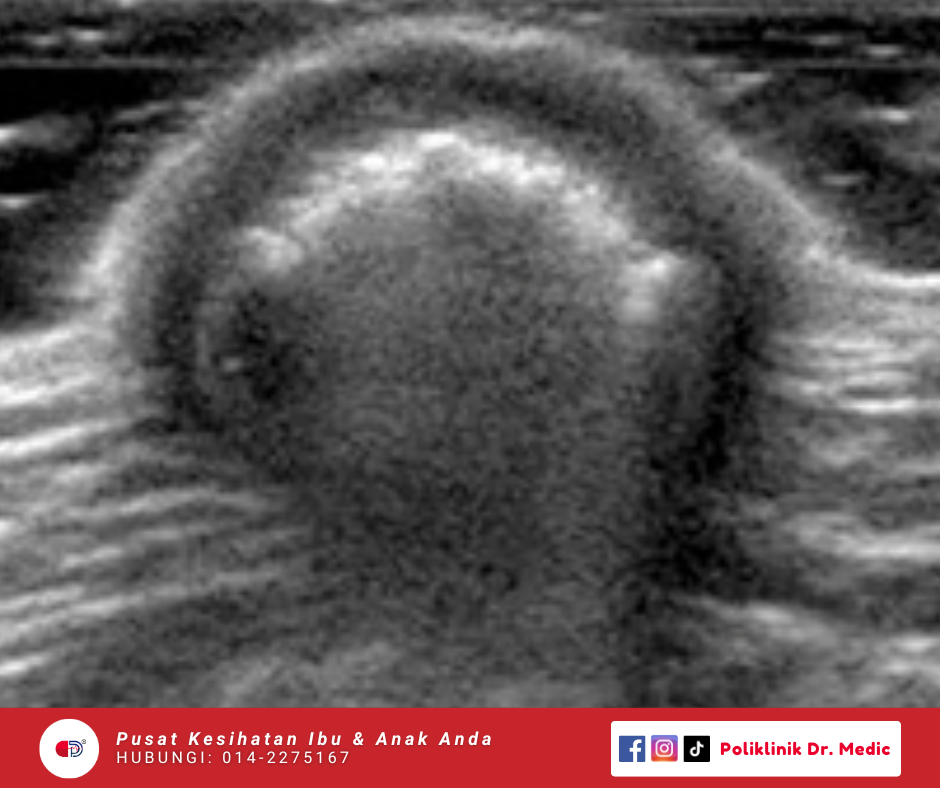

superficial (Lump & Bump)

Kawasan Pemeriksaan pada ketulan di kulit atau tisu luar seperti di leher, ketiak, lengan, perut, paha atau mana-mana bahagian badan. Pemeriksaan ini membantu mengenal pasti sama ada ketulan tersebut berpunca daripada sista, lipoma (ketulan lemak), pembengkakan kelenjar, jangkitan atau perubahan tisu yang tidak normal.